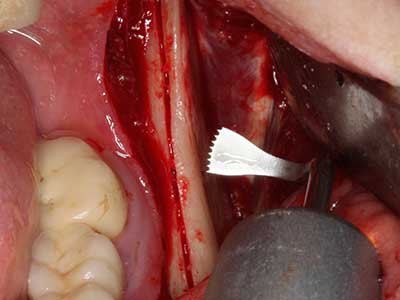

Indication: Preparation near nerves

As noted above, indications for piezosurgery can also be found in the field of conservative dental surgery. Special working tips simplify the exposure of root tips and make it easier to protect nerves and sinus mucous membranes, particularly in the lower premolar and upper posterior tooth regions. Angled diamond tips are used to precisely prepare the resection cavity for the retrograde root filler material for unsealed apical obturation. The ultrasonic technology means the tips can be very slender, which improves the view and the size of the access cavity. As a result, the application of ultrasonic surgery for this indication is one of the standard procedures for apical resection (Del Fabbro, Tsesis et al. 2010, Scarano, Artese et al. 2012).

Indication: Apical resection

When surgical procedures are performed on bone in the immediate vicinity of sensitive structures such as blood vessels or nerves, rotary instruments pose a significant risk of iatrogenic injury. Piezoelectric devices can be helpful for preparation of bone covers and removal of hard tissue close to nerves, particularly for exposure of nerves after iatrogenic injury but also during nerve lateralization for resective and reconstructive procedures or implant placement (Fig. 17-20). Light contact between the piezotip and the nerve does not generally result in damage but proceeding incautiously with saw-like motions or attachments where a residual bone substrate remains may cause temporary or even permanent nerve damage. However, the risk of damage is considered to be substantially lower than when using saws or milling instruments (Pereira, Gealh et al. 2014).